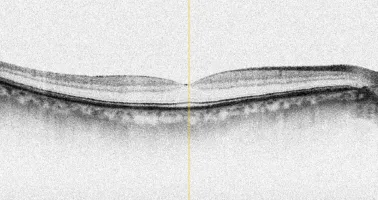

Das Coverbild der November-Ausgabe von OCL: ein OCT einer Makula